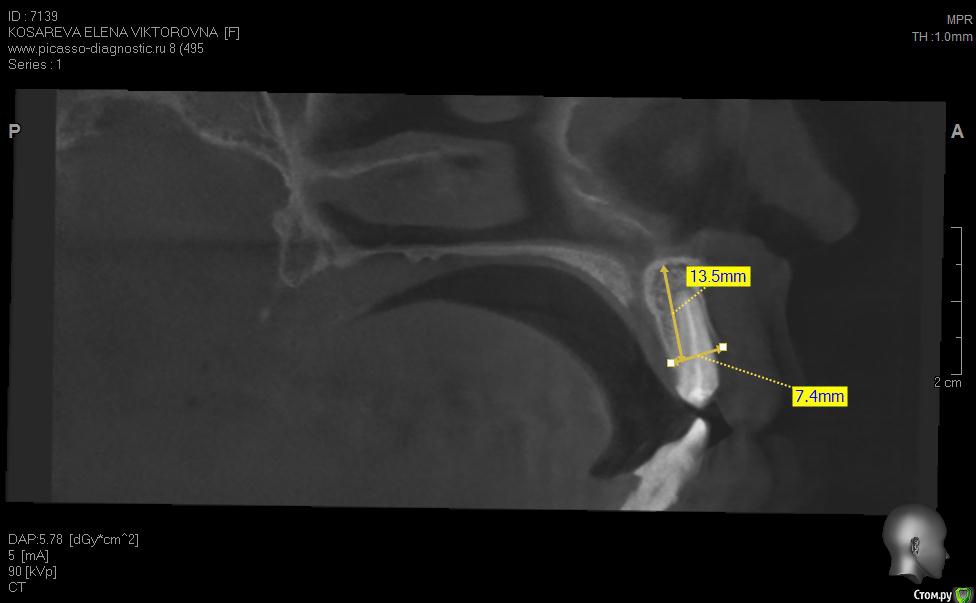

Уважаемые коллеги помогите пож с планом лечения, хотелось бы услышать ваши планы лечения,

пациент хочет красивую улыбку и импланты, клыки трогать категорически отказалась как опоры под временные на период интеграции имплантов